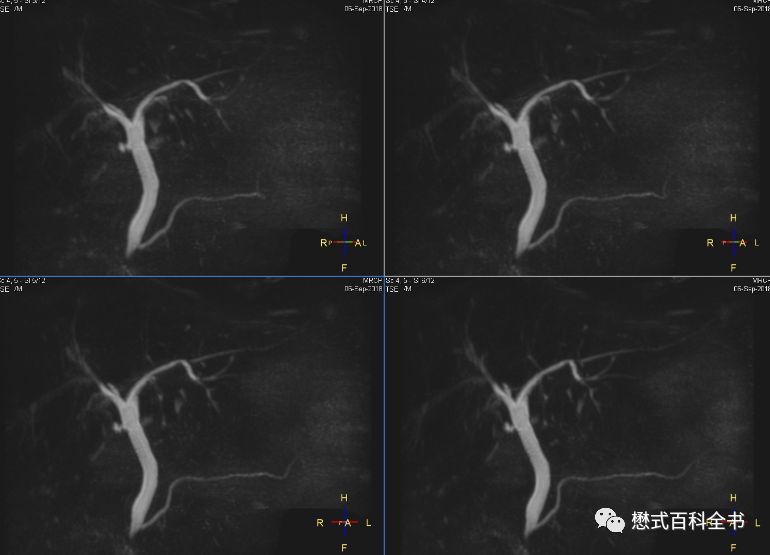

图22:2D MRCP扫描

如图,2D单激发MRCP扫描。一次激发采集一层或者多层。

2D MRCP优点是:扫描速度快。一次激发采集1层或者多层,直接出图像,能够很好的显示结石的充盈缺损。

缺点是:信噪比比3D的低,一次扫描出1~几层,单层层厚厚,有部分容积效应。

所以,理论上为了保证好的诊断效果,我们推荐3D MRCP和2D ssh MRCP都要扫描。当然,3D MRCP扫描完,一定要看原始薄层图像,有经验的诊断医生不可能只看MIP图去诊断。